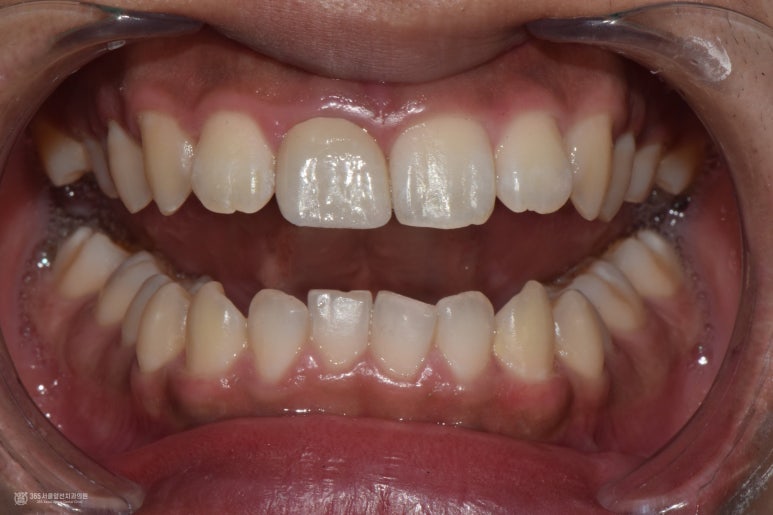

촬영일시 : 2024.10.15 또한 앞니 보철물도 새로 잘 만들어드렸습니다. 고름주머니도 소실되었고 통증도 사라졌습니다ㅎㅎ 오늘 소개해 드린 주안동치과추천 365서울앞선치과의원 치료 증례는 오래전 신경치료된 치아에 염증이 재발하여 재신경치료를 하여 치아를 살린 치료입니다. 재신경치료는 난이도가 높은 치료 술식에 해당하므로 전문가와 충분한 상의를 거친 후 치료를 받으시는 것이 중요하겠습니다 ㅎㅎ 앞으로도 좋은 치료 증례로 찾아뵙겠습니다. 감사합니다 ㅎㅎ [치료기간: 2024년 9월13일 ~2024년 10월15일] ※365서울앞선치과의원의 모든 포스팅은 각 진료과 의료진이 직접 작성합니다. 365서울앞선치과의원 블로그의 임상 케이스 게시물은 환자분께 의학적으로 정확하고 상세한 정보를 드리기 위해 각 진료과 의료진이 직접 작성하며, 모든 증례 사진은 본원 의료진이 직접 시술한 증례를 촬영한 것으로, 의료법 제23조, 제56조에 의거하며 환자분의 동의를 얻어 포스팅에 사용하였습니다. 또한 해당 케이스는 본 환자분의 치료 결과이며, 환자 상태에 따라 치료의 결과는 달라질 수 있습니다. |